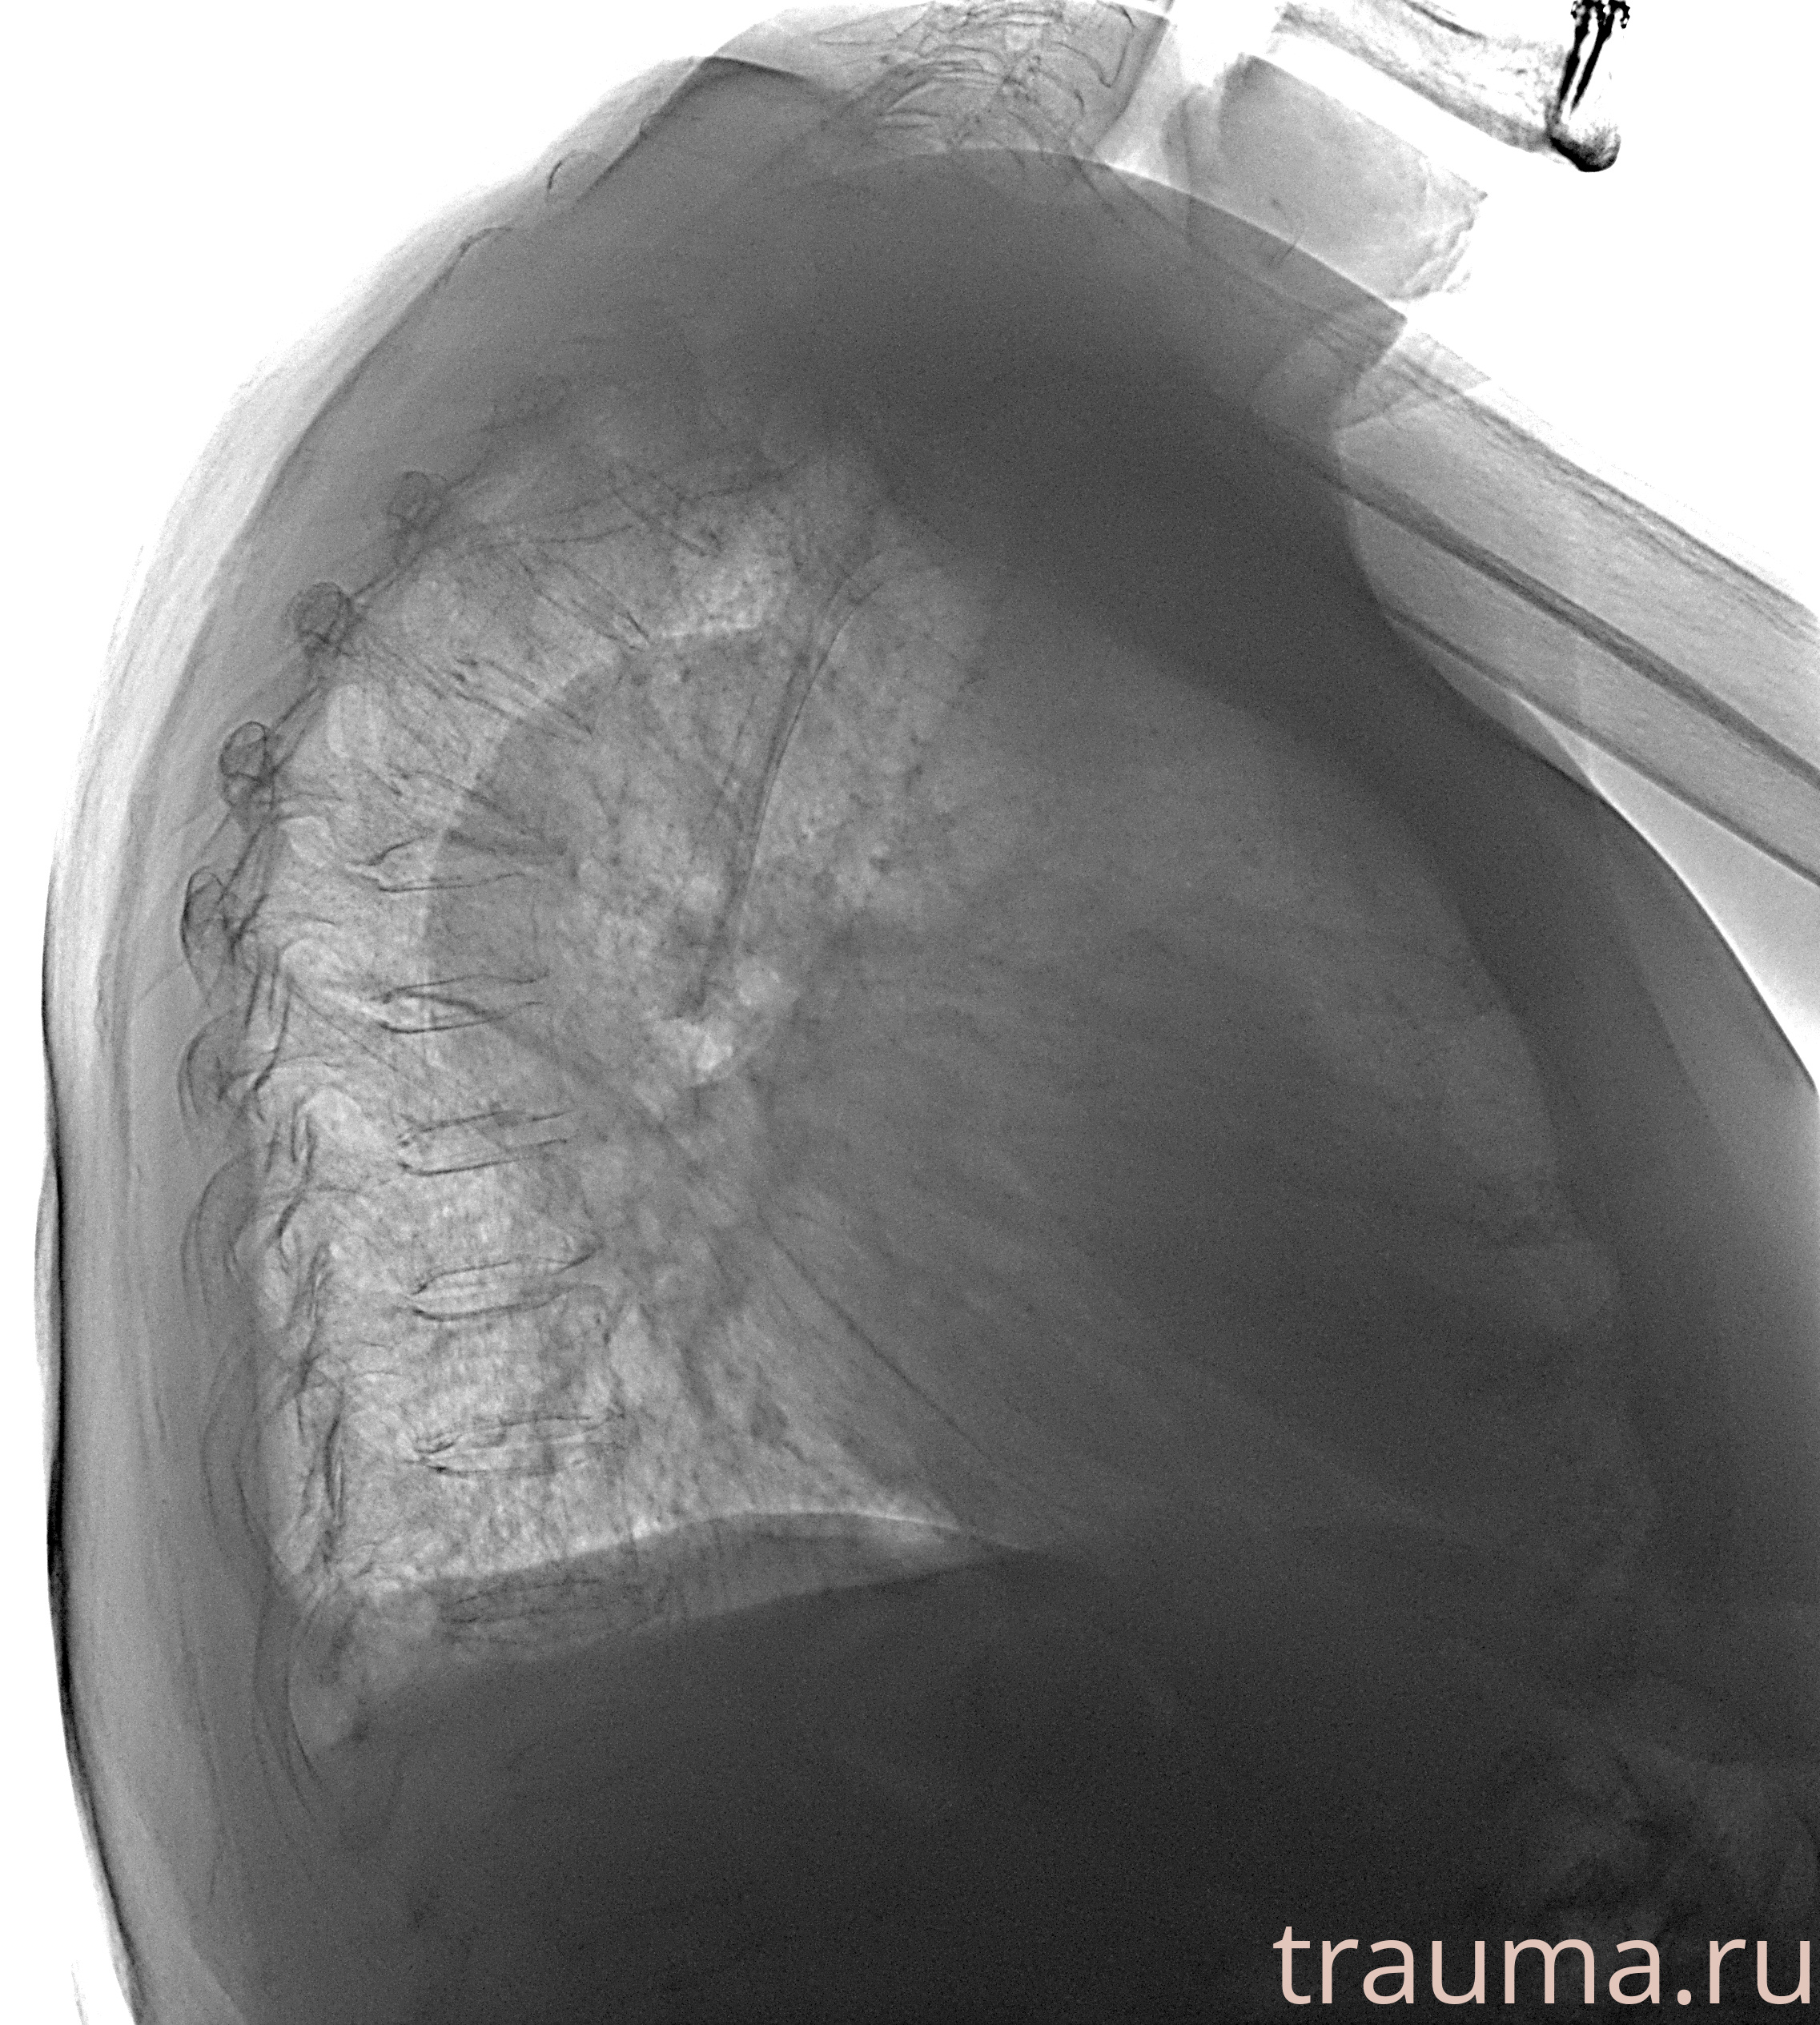

Рентген на дому: по вашему адресу приезжает врач-рентгенолог, травматолог-ортопед с мобильным рентгеновским аппаратом, проводит диагностику травмы или заболевания, делает необходимые рентгенограммы, дает рекомендации по дальнейшему лечению. Получить качественные снимки в домашних условиях возможно благодаря уникальной методике, разработанной МосРентген Центром для института  Склифосовского

при переломе шейки бедра и пневмонии от компании МосРентген Центр - партнера Института имени Склифосовского